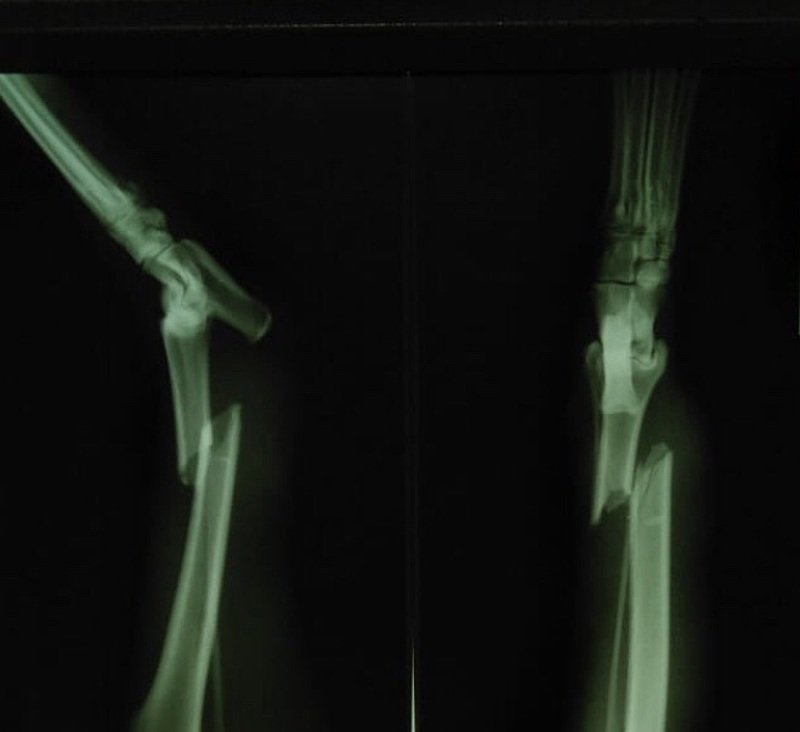

A Babi foi atropelada e permaneceu sem socorro até ser resgatada por um abrigo de animais em Petrópolis.  Conseguimos estabilizar a fratura exposta, porém  precisamos o quanto antes de R$ 1.500,00 para a cirurgia ortopédica e para anestesia ver tudo

A Babi foi atropelada e permaneceu sem socorro até ser resgatada por um abrigo de animais em Petrópolis.  Conseguimos estabilizar a fratura exposta, porém  precisamos o quanto antes de R$ 1.500,00 para a cirurgia ortopédica e para anestesia. No momento ela está à base de analgésicos para suportar a dor,  na esperança de que vaquinha consiga arrecadar o valor necessário.